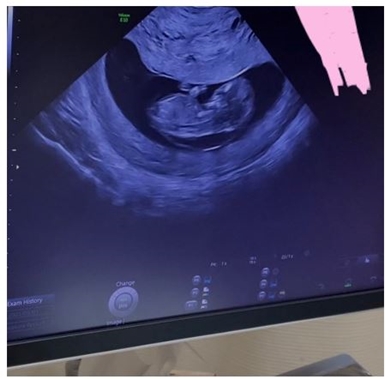

2022年12月、1歳の娘を子育てしながら息子を妊娠中だったころに、ダウン症の可能性が50%あると医師から指摘されていたことを明かしていた光上さん。出生前診断を受け息子に染色体異常がないことが判明したそうですが、成長過程でヌーナン症候群の可能性を指摘されたと伝えていました(関連記事)。

その後の検査で、「結論としてはまだわからないでした」と確定診断に至らなかったとしながらも、「可能性が0にはできないと言われてしまった」と明かし、今回は遺伝子検査をしなかったともつづっています。

光上さんによると、遺伝子検査をしなかった理由は「身長に関しては経過観察が必要」だったからとのことで、ある程度体が成長した2歳になる前に検査するとのこと。また、血液検査では全く異常がなく体が同年齢の子どもたちよりも小さい原因が判明しなかったことから「やっぱりヌーナン症候群の可能性も視野に入れていかなければならない」と指摘されたそうで、「めちゃくちゃ泣きそうになったけど、グッと堪えて、わかりました、と言った」とショックを受けた当時の様子を振り返りました。